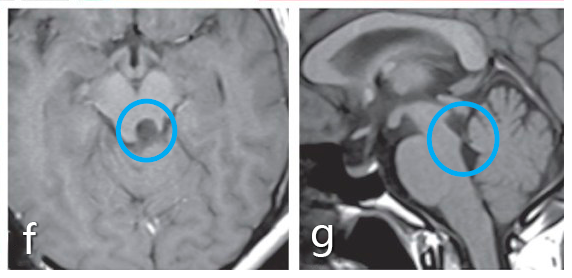

術(shù)前:a、b圖術(shù)前MRI顯示中腦頂蓋占位,腫瘤導(dǎo)致導(dǎo)水管閉塞。

a、b圖術(shù)前MRI顯示中腦頂蓋占位,腫瘤導(dǎo)致導(dǎo)水管閉塞。

術(shù)后:f、g圖術(shù)后MRI影像顯示腫瘤得到了全切?;颊邿o并發(fā)癥,無其他神經(jīng)系統(tǒng)缺陷。術(shù)后病情平穩(wěn),術(shù)后5年內(nèi)無腫瘤復(fù)發(fā)。